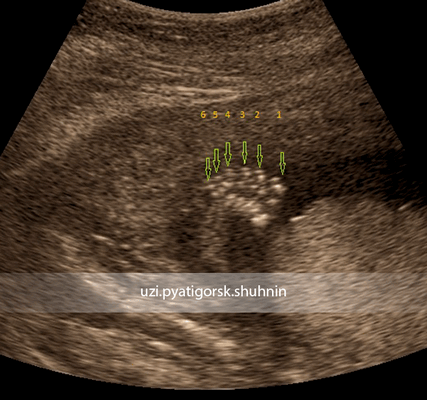

Стопа плода в норме

Постаксиальная полидактилия, визуализирован дополнительный 6-ой палец стопы плода